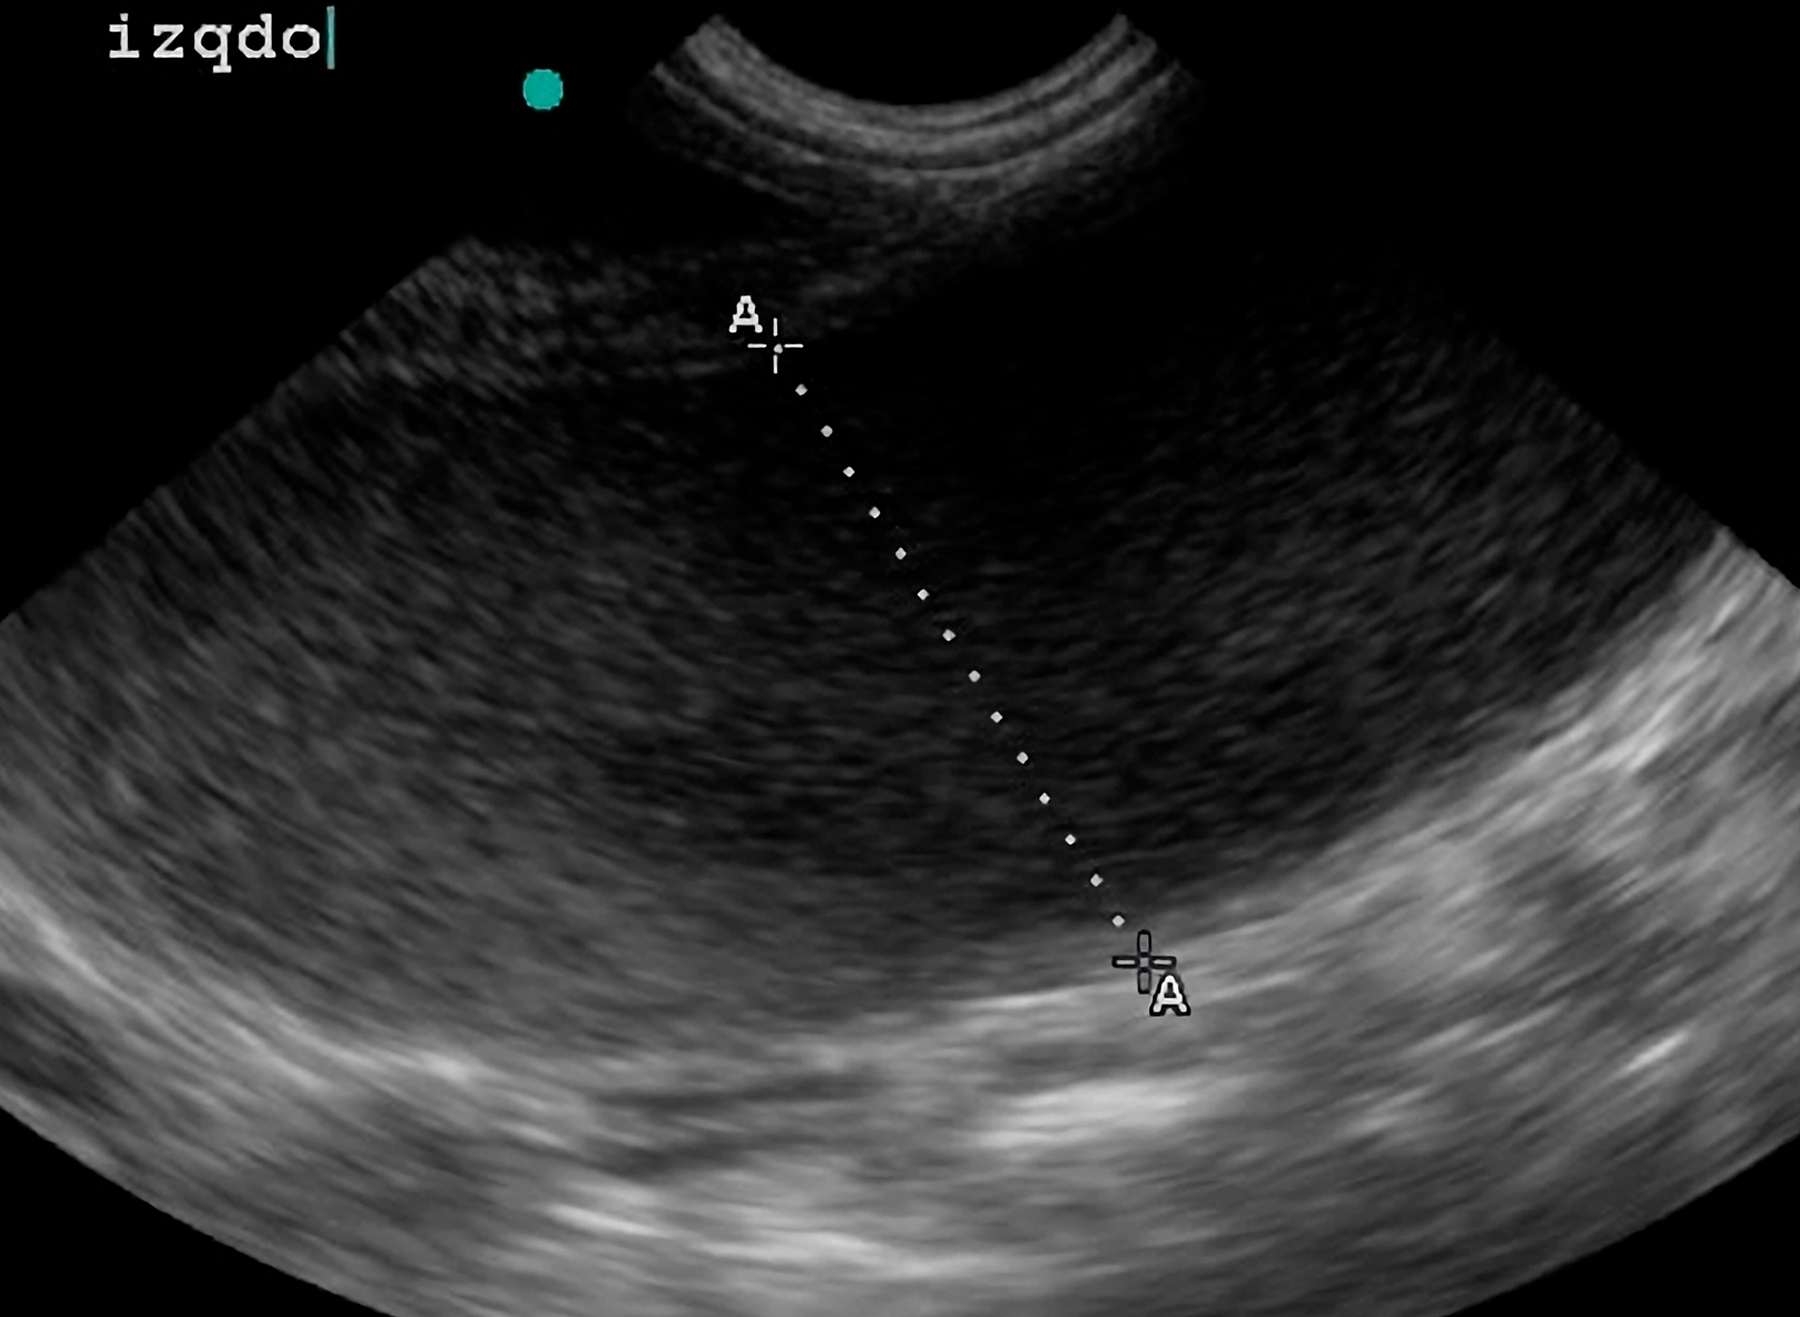

Estudio Ecográfico Especializado:

Se identificó una distensión abdominal marcada con presencia de contenido líquido patológico compatible con proceso uterino.